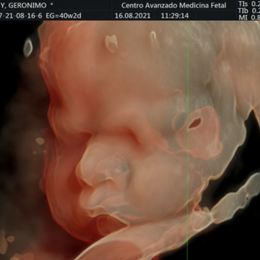

- La calidad de los resultados depende en gran medida de la habilidad del

técnico o del médico, lo que no sucede en el caso de la CT o MRI.

- En las personas obesas resulta más difícil obtener buenas imágenes.

- Las formas nuevas de ecografía pueden proporcionar imágenes en 5-D.